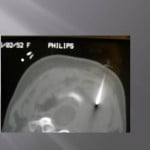

Biopsie sous guidage scanner